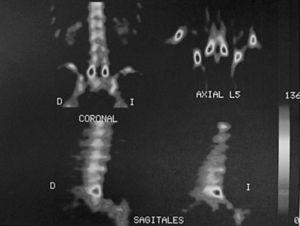

A los 15 días el paciente se presenta con sintomatología atenuada. La GOP/SPECT (figs. 4 y 5) demuestra fenómenos de remodelación ósea a nivel de ambas pars de L5. Por tanto, se concluye el diagnóstico de espondilólisis activa L5 derecha y espondilólisis izquierda en formación. Se continúa el mismo tratamiento agregándose una pauta específica de ejercicios delordosantes y ortesis plantares de corrección.

Figura 4

Figura 5